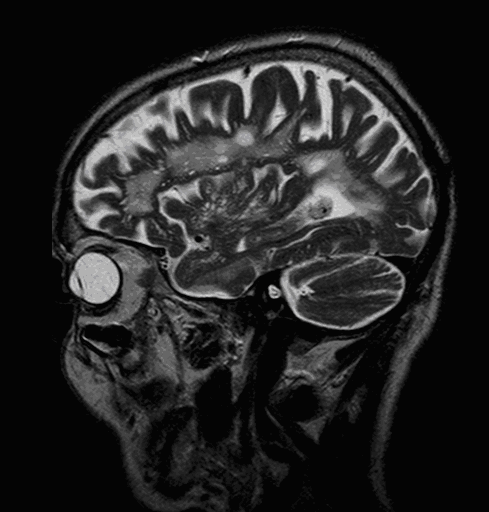

10.1.2.4. Magnetic Resonance Imaging (MRI):

It provides excellent tissue contrast, making MRI the distinguished imaging method of the central nervous system. However, availability is still limited (only a few number of 24 hour on-call centers) and patients often cannot schedule for a necessary MRI examination on time.

As opposed to the volumetric data acquisition of CT scanning, MRI has the advantage that its image production is not distracted by bony artefacts.

White matter lesions, old hemorrhages (hemosiderin) can only be depicted with MRI.

Diffusion weighted MRI (DWI) is the most sensitive method in the detection of early stroke. Diffusion weighted imaging is also able to take measurements of the movement of protons along the fiber tracts of the brain, thus enabling the visualization of cerebral white matter tracts.

MRI provides even more definitive proof. On T1 weighed images they are usually hypointense, on T2 weighed images their signal is strong. Although these signs are very characteristic, normally they are still insufficient for exact differential diagnostic criteria.

MRI has the greatest sensitivity in the detection of neoplastic brain lesions. The relaxation time of tumor is usually longer than that of the surrounding normal tissues. Therefore on T1W images neoplasms have slightly weaker signal intensity, while on T2W images they are more hyperintense than normal parenchyma. This signal pattern can be very characteristic and has great diagnostic value. However, secondary neoplastic signs, such as mass-effect of the tumor cannot be neglect either. A space occupying lesion can cause:

The method of choice for the imaging of multiple sclerosis is MRI. MS lesions secondary to their increased water content appear as increased signal intensity lesions on (T2 weighted), PD images and on FLAIR sequence.